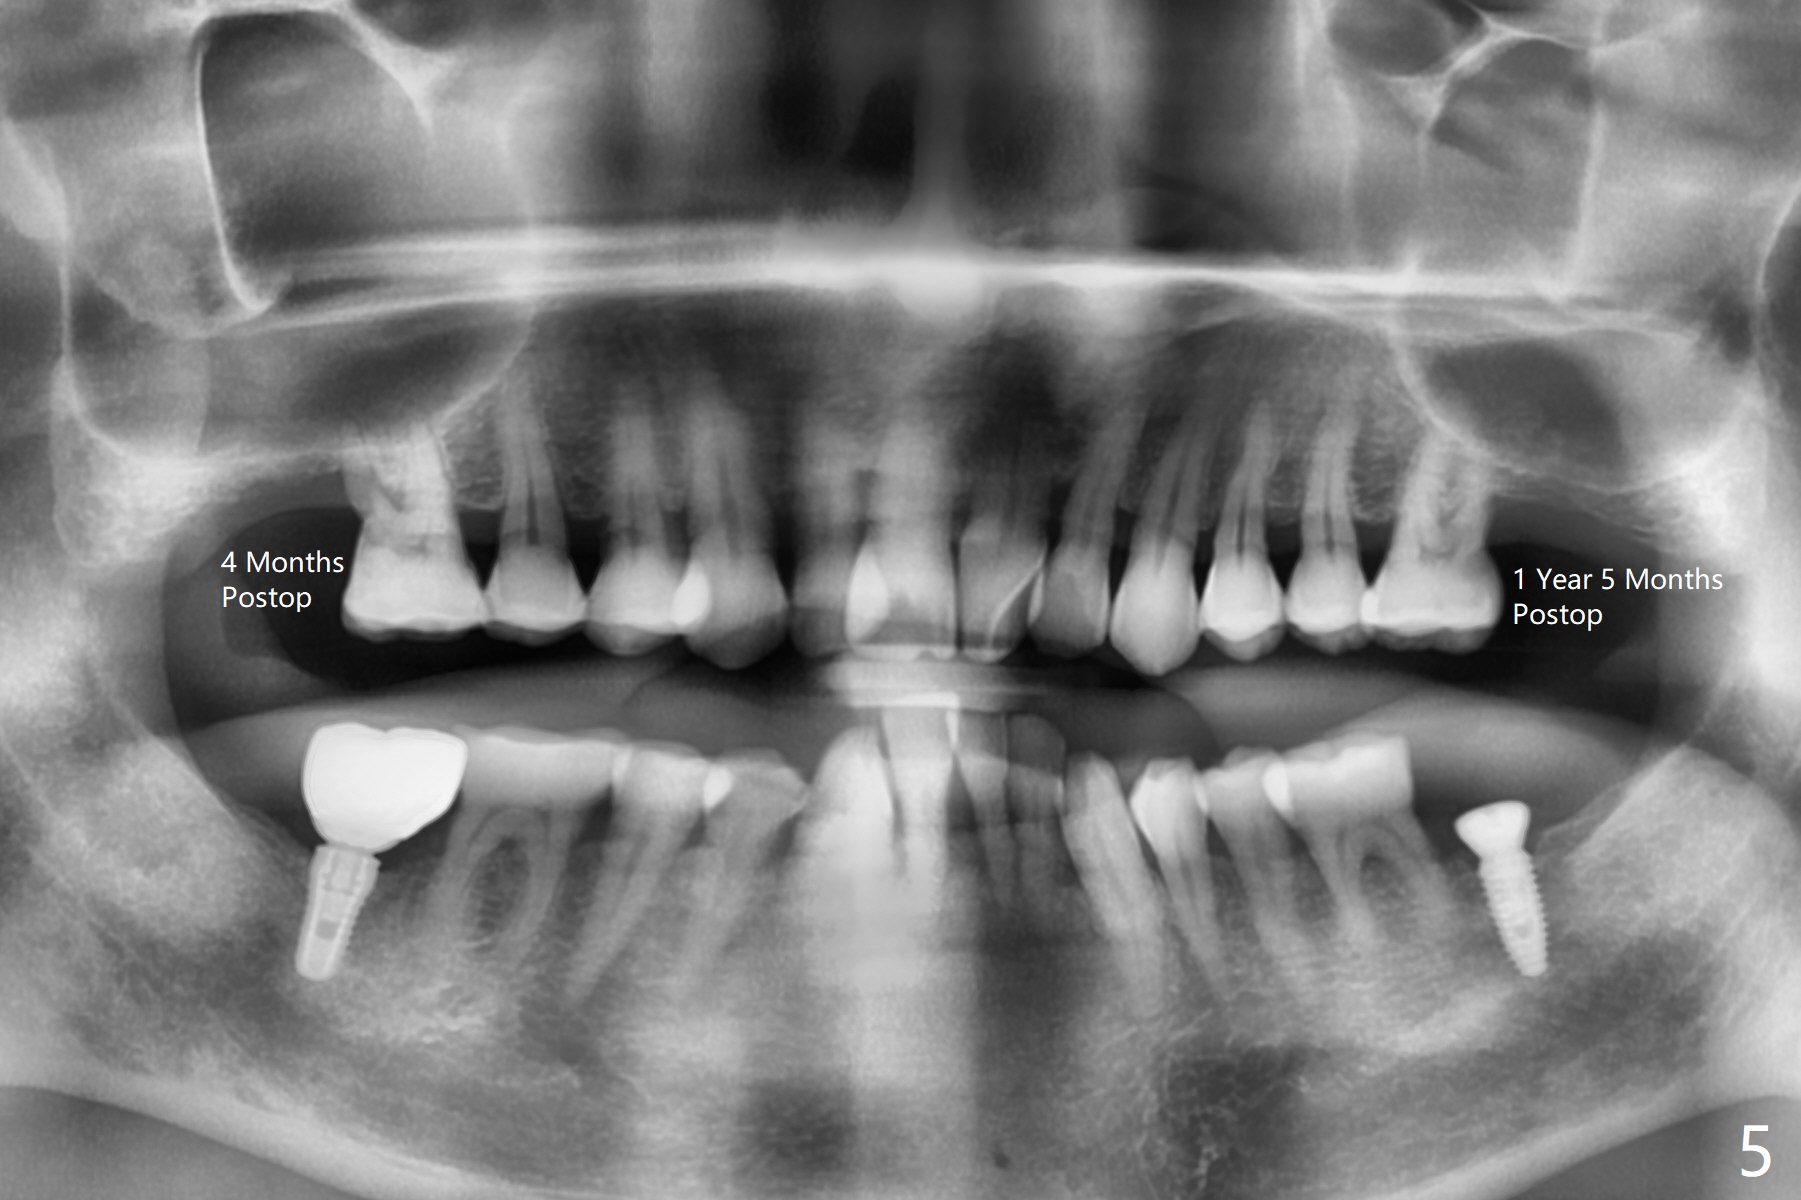

50岁男,二型糖尿病,对常用糖尿病药物无效,使用胰岛素也必须提高剂量,总之控制不好。总共种植四个,两个延期没问题,但是两个即刻均失败,似乎容易发炎,包括右上7(图一:* (螺纹暴露)),颊侧牙龈退缩(图二),牙冠取出后显示植体和基台偏腭侧(图三:P),其实植体没有整合,不费劲旋出植体,清除肉芽组织后,植入粘性骨粉(图四:*),覆盖PRF膜,GEM Cap,应用牙周胶水固定,然后间隙维持器,牙周敷料固位。右上7和左上7植牙取出后4个月和一年5个月骨质高度很低(图五)。右上7大约1.8毫米(图六)。准备植入5x7毫米植体(图七)。使用1毫米stopper钻头,然后Magic Lifter和PRF。术前口服Z Pack,术后Medrol Dose Pack。